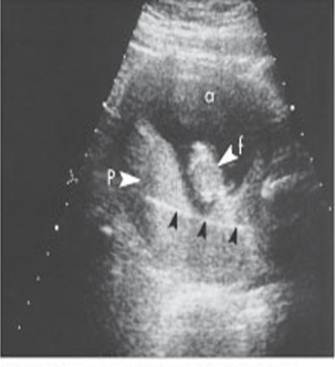

Poli-Oli sequence (stuck twin)